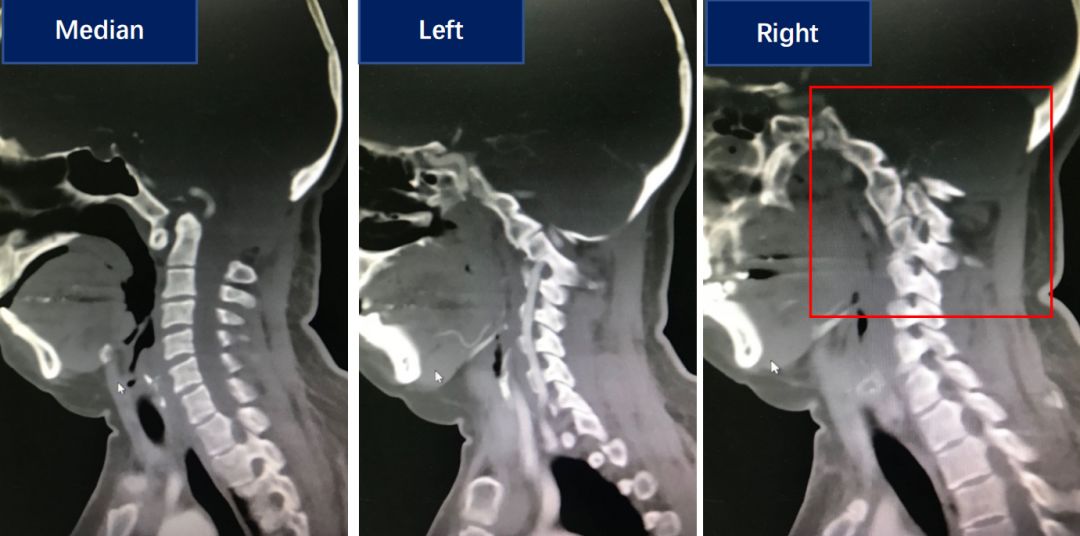

术前CT显示病人有明显的齿状突内陷,同时有双侧侧方关节的发育畸形。

术后患者颅底凹陷得到改善,同时斜坡颈椎角也有明显恢复,右侧绞索的侧方关节得到复位。

对比术前和术后的矢状位CT,可见齿状突内陷明显改善。